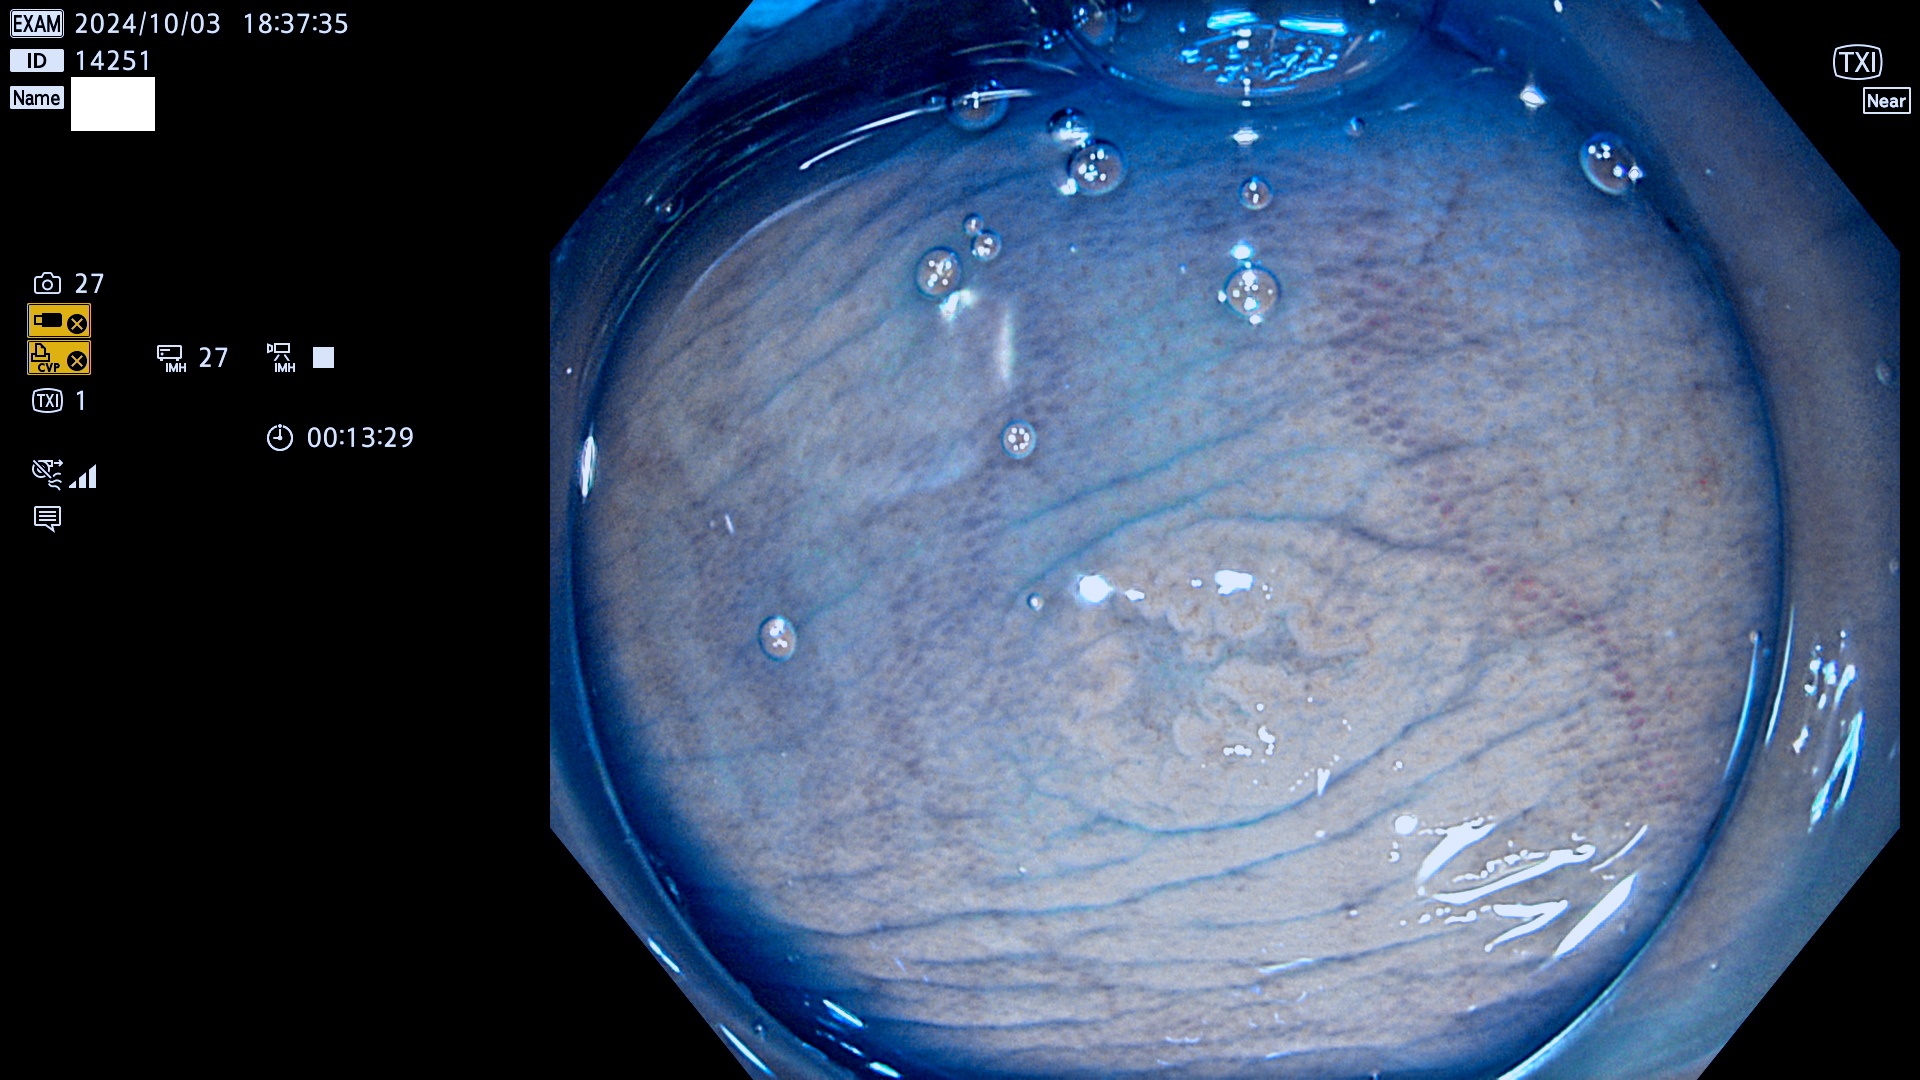

今週のUb、Uc型腺腫

完全に平坦な物をUb、陥凹している物をUcと呼びます。最も発見が難しく危険な病変です。

毎週の検査(木・金・土・日)に発見されたUb、Uc型・腺腫を、その週の日曜の夜にUPし1週間、提示します。

抽出の対象期間 2024年10月3日〜10月6日の4日間(48件の検査)9件 (9/48=18%)